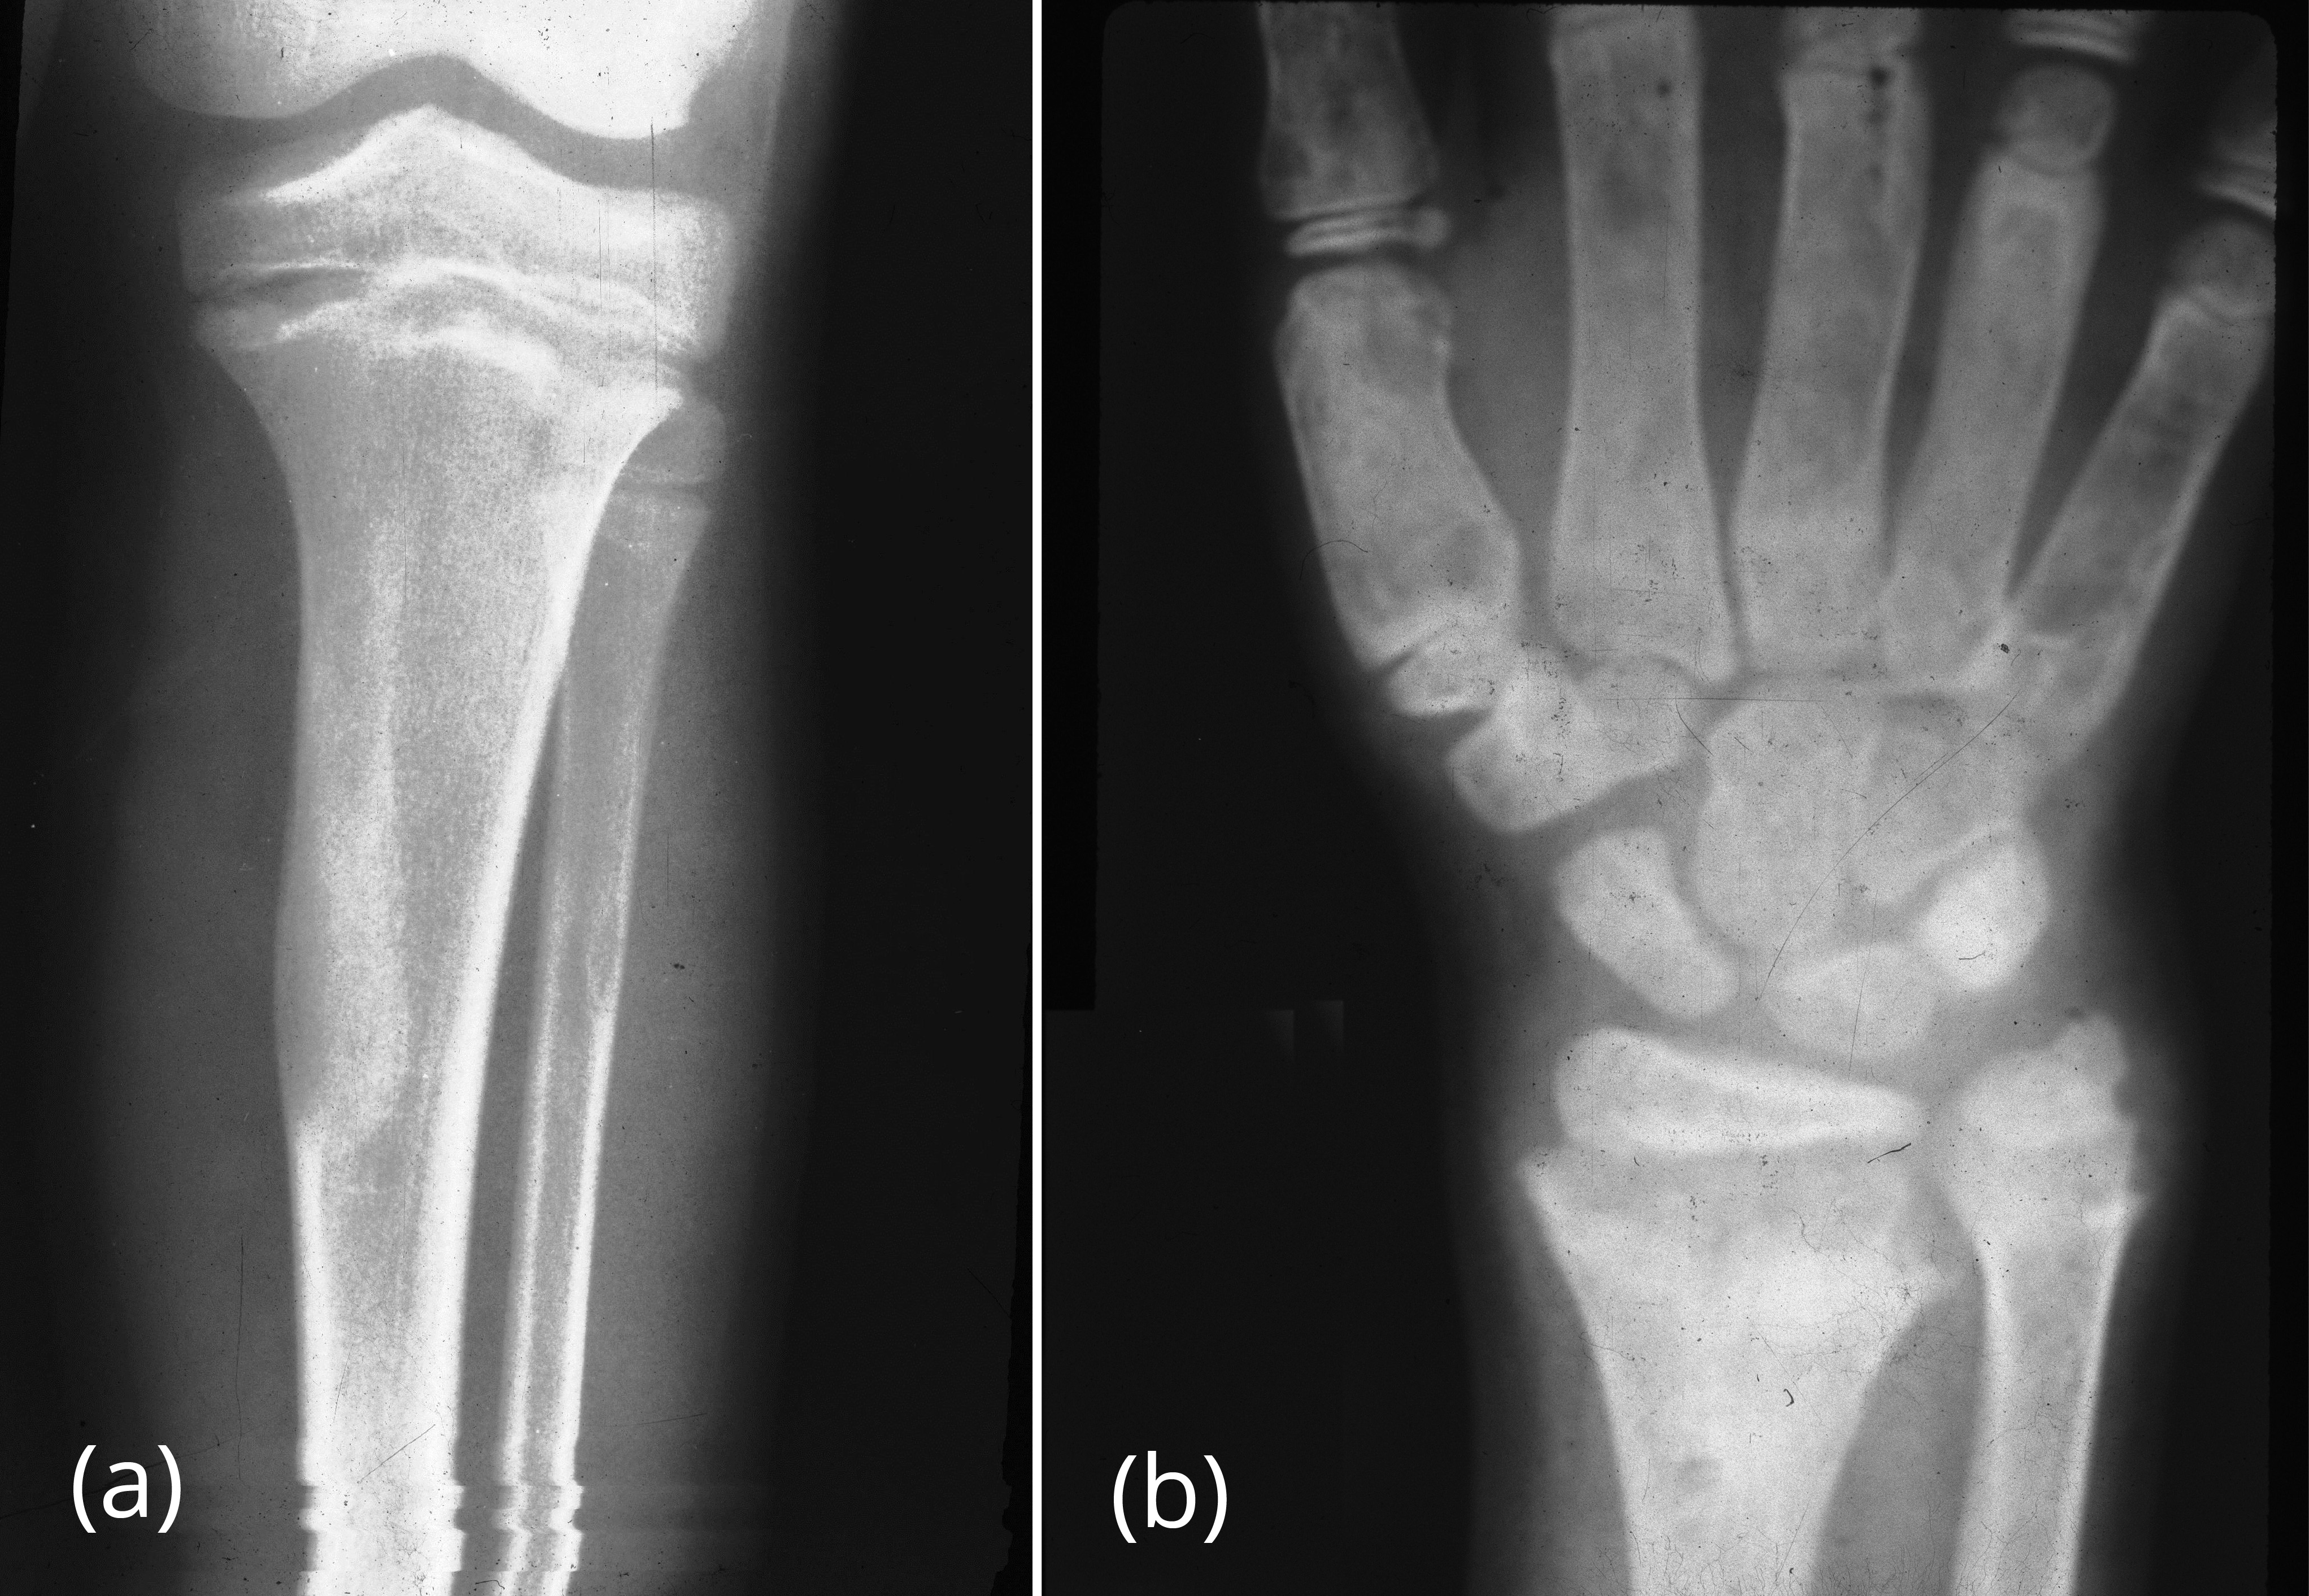

Complications

Not surprisingly bone affected by fibrous dysplasia is weaker than normal and thus susceptible to pathological fractures. Occasionally, rickets in children and osteomalacia in adults in encountered with fibrous dysplasia due to unknown humoral mechanism (Figure 28a,b).

Figure 28: (a) FD of proximal tibia with rachitic changes with increased distance between metaphysis and epiphysis of tibia, (b) FD metacarpals with rachitic changes, cupping of the radius and ulna of the wrist in a 7 yr old boy.